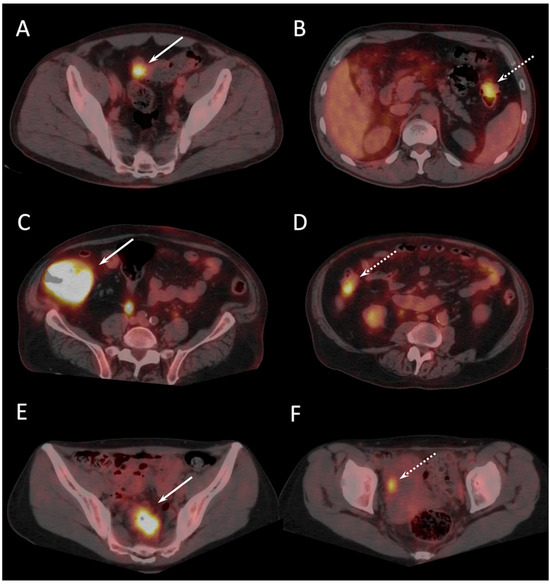

| S (T3) | 55 | TP | TP | Detection of two additional synchronous invasive adenocarcinomas beyond a sigmoid tumoral stenosis |

| LC (T2) | 25 | FN | TP | |

| C (T2) | 30 | FN | TP | |

| S (T3) | 70 | FN | TP | Detection of one synchronous invasive adenocarcinoma not reported at colonoscopy |

| CG (is) | 60 | TP | TP | |

| S (T3) | 45 | TP | TP | Detection of one synchronous invasive adenocarcinoma not reported at colonoscopy |

| S (T3) | 25 | FN | TP | |